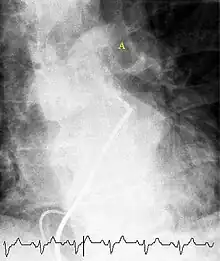

Ventilation/perfusion scan

(A) After inhalation of 20 mCi of Xenon-133 gas, scintigraphic images were obtained in the posterior projection, showing uniform ventilation to lungs.

(B) After intravenous injection of 4 mCi of Technetium-99m-labeled albumin, scintigraphic images shown here in the posterior projection. This and other views showed decreased activity in multiple regions.

A ventilation/perfusion scan (or V/Q scan or lung scintigraphy) shows that some areas of the lung are being ventilated but not perfused with blood (due to obstruction by a clot).[17] This type of examination is as accurate as multislice CT, but is less used, due to the greater availability of CT technology. It is particularly useful in people who have an allergy to iodinated contrast, impaired kidney function, or are pregnant (due to its lower radiation exposure as compared to CT).[56][57][58] The test can be performed with planar two-dimensional imaging, or single photon emission tomography (SPECT) which enables three-dimensional imaging.[49] Hybrid devices combining SPECT and CT (SPECT/CT) further enable anatomic characterization of any abnormality.